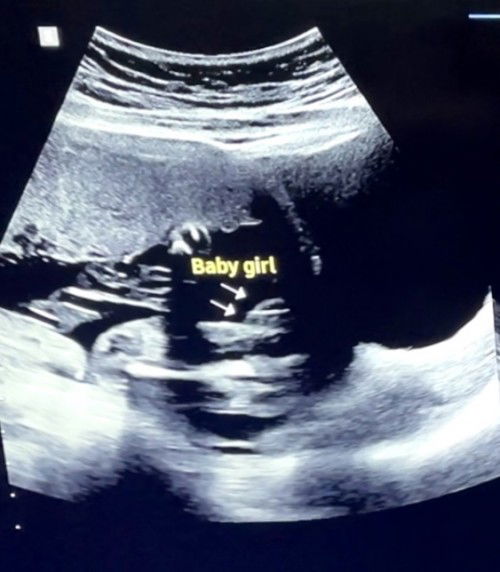

Confirm na bang baby girl?

Hello mga mommies! Baby girl na ba talaga si baby ko? Pahingi naman po opinion nyo. Salamat 🥰🤗#pregnancy

Yes po, girl po yan. If boy po kasi, kita po agad ung lawit and balls.